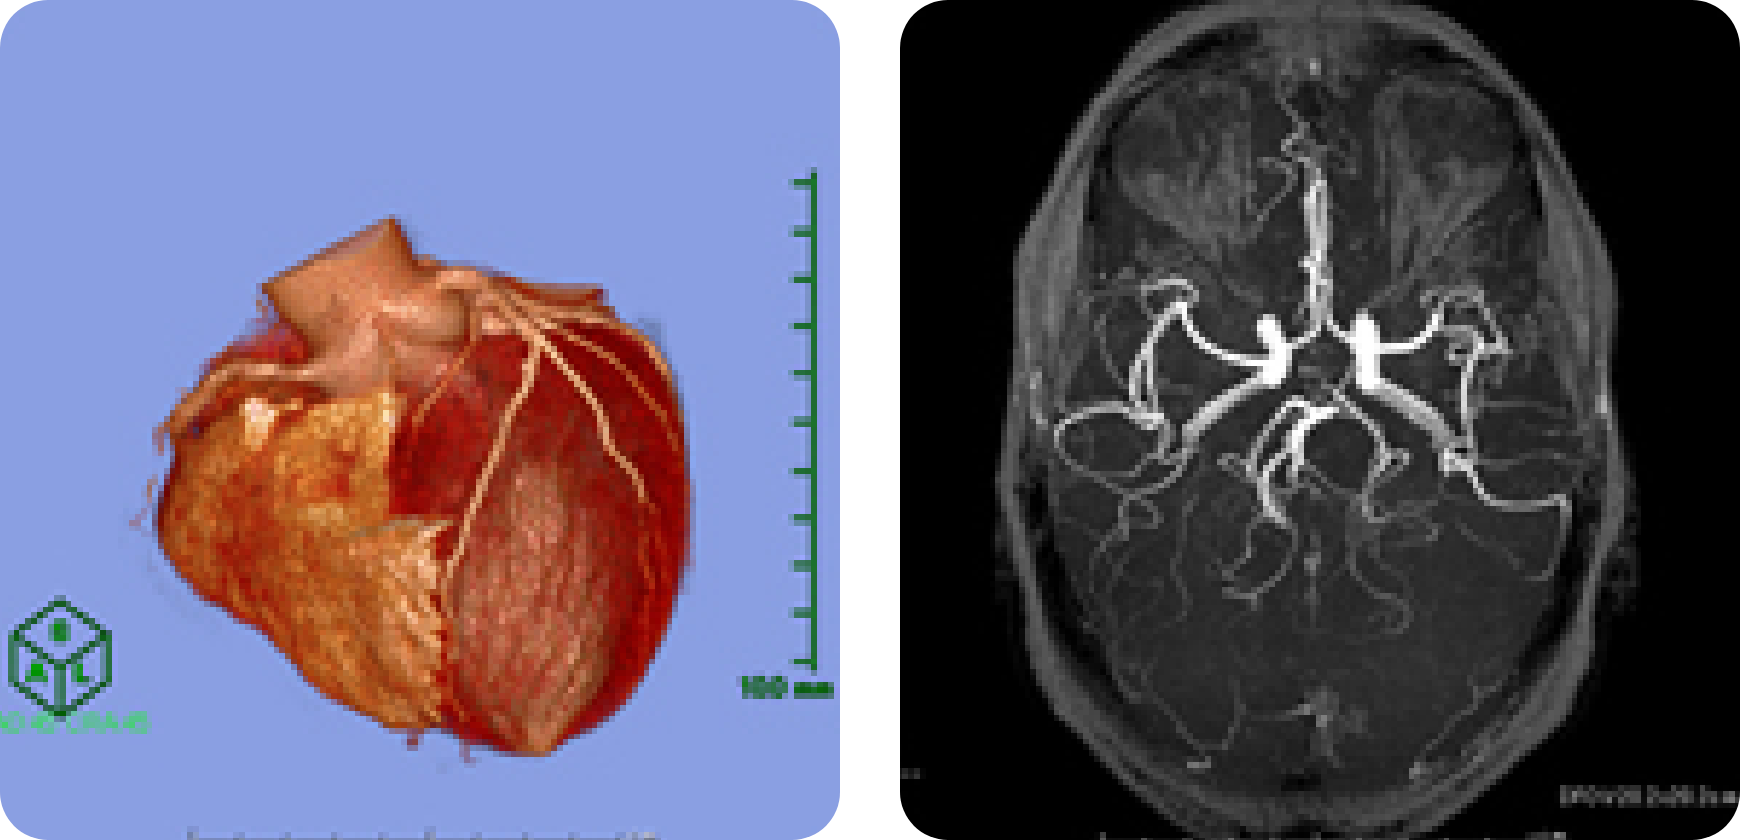

CTは画像診断のエースといってよい存在です。近年のCT機器・画像処理技術の進歩は目覚ましく、多数の検出器を搭載したマルチスライスCTが標準となっています。これに加えて最近ではdual-energy scanという新しい技術を搭載されたCTも開発されています。岡山大学病院では320列をはじめとする5台のマルチスライスCTが稼働しており、うち2台ではdual-energy scanによる腫瘍や結石の成分分析が可能となっています。また2017年5月からは、世界に先駆けて国内導入された超高精細CT装置「Aquilion Precision」も稼働しています。これらのCT装置は従来よりも短時間で、より細かな画像撮影が可能な優れた画像診断装置です。病気によってはヨード造影剤を静脈から注射しながらCTを撮影することがありますが、より詳細な質的情報を得ることができます。また心臓領域や脳神経領域では、以前はカテーテル検査でなければわからなかった冠動脈や脳血管の評価がCT撮影にて行えるようになりました。更にコンピュータの進歩によって、視覚的に理解が容易となる三次元画像も各診療科に提供しており、外科手術のナビゲーション用としても広く使われるようになってきています。

MRIは磁気を用いて体内の状態を画像化する装置であり、CTとはまた異なった情報を与えてくれます。当院では現在5台のMRI装置が稼働しており、うち3台は3テスラの高磁場装置です。MRI画像は組織分解能が高いことが特徴のひとつであり、腫瘍など病変部の性状を詳しく分析することが可能です。また、中枢神経領域では脳梗塞の早期診断に欠かせない診断装置であり、造影剤を用いることなく脳血管を評価することもできます。CTに比べて検査時間が長くまた検査中に大きな音がすることが欠点ですが、CTのようにX線を使いませんので放射線被ばくはありません。

【大動脈弓離断症 3D-CT】

肺炎や炎症性腸疾患、腸閉塞、外傷、先天性心疾患、小児悪性腫瘍などの画像診断を行っています。

最新のCT機器での撮影では医療被ばくの低減も心がけています。